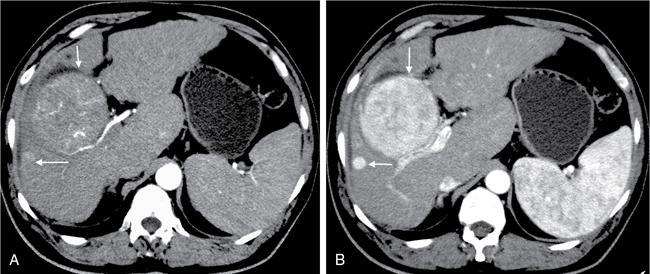

Samarjit Ghuman, Seema Sud, Deeksha Rastogi, Swapnil Sheth, T.B.S. Buxi PLAIN RADIOGRAPHY FOR HEPATOBILIARY IMAGING The diagnostic imaging techniques for hepatobiliary imaging can be intimidating with many techniques/modalities providing the information desired. The job of the diagnostic radiologist includes being familiar with the available choices and pick the ‘best fit’ keeping in mind the pros and cons of each modality, which includes plain X rays, Contrast studies using plain X rays and fluoroscopy, Ultrasound includiojng Doppler and Ultrasound elsastography, CT including multiphase CT and MRI and MRI elastography. Understanding the strengths and weaknesses of every modality as well as the ability to tailor each study individually will help to optimise patient cares. The abdominal radiograph is performed almost exclusively in the supine position and in the AP (anteroposterior) projection. In case of acute abdomen, an erect chest radiograph should also be performed to look for free air under the diaphragm. The standard abdominal radiograph should extend from the diaphragm to the inferior pubic rami, and includes the lateral abdominal wall musculature. Routinely no preparation is required for abdomen radiograph done for hepatobiliary imaging. The radiograph has limited soft-tissue contrast, however, the liver being the largest intra-abdominal organ, casts a perceptible shadow. The margins of the liver can indirectly be seen by outline of adjacent organs like lung, hemidiaphragm, pro-peritoneal fat line, kidney and gas shadows of stomach/colon. The right lobe is seen better than the left lobe of liver. The following pathologies may be visualized on the plain radiograph of the liver. Liver enlargement Liver mass Calcification Increased radiodensity of the liver Decreased radiodensity of the liver An ultrasound is the first line investigation; however, a radiograph may be done for routine evaluation of abdominal pain. The following pathologies may be seen on plain radiograph of the biliary tree. Calculi and Calcifications Gas ULTRASOUND OF HEPATOBILIARY SYSTEM Ultrasonography (USG) is the initial imaging modality of choice for scanning hepatobiliary system. USG is accurate and has high sensitivity and specificity in diagnosing biliary pathologies. Table 9.1.1 shows indications of ultrasound in hepatobiliary system. The real-time nature of ultrasound lends itself to demonstrate mobility of calculi and sludge and the sonographic Murphy sign can easily be elicited during scanning. The main disadvantage is operator dependence, patient’s body habitus, presence of gas which can obscure the visualization of organs, overlying bandages in a postoperative patient and incomplete evaluation in a nonfasting state. USG of upper abdomen should be done after 6–8 hours of overnight fasting. Milk and fatty food should be avoided as they cause contraction of the GB and may cause the GB walls to appear thickened. History of previous surgery, especially cholecystectomy should be elicited. The patient may be positioned in supine or left lateral decubitus position. The GB can be scanned from a high/lateral view, looking through the ribs in supine position or through a sub-costal view in left lateral decubitus position. Position of patient may be changed to demonstrate mobility of structures. The GB is an anechoic structure which is located in the GB fossa along the posterior and inferior aspect of the liver. It has a fundus, body and a neck. It should always be examined in at least two planes (Fig. 9.1.6A and B). The wall of the normal GB should measure 3 mm or less and pathological GB wall thickening can be due to cholecystitis or a neoplastic aetiology. Calculi appear as mobile hyperechoic foci, with distal acoustic shadowing. Other pathologies include polyps and sludge which can be differentiated on the basis of their mobility. The CBD measures less than 6 mm in diameter with increase in the diameter with patient’s age and after cholecystectomy. The CBD is usually scanned in an oblique subcostal plane with the patient in the left decubitus position (Fig. 9.1.7). Dilatation of the intrahepatic biliary radicles is readily assessed with USG and normal intrahepatic biliary radicles are usually not appreciated on USG. Ultrasound of the liver, broadly, is done to assess the size, surface (smooth, coarse or lobulated) parenchymal echogenicity (increased or decreased) vascularity and for presence and evaluation of intrahepatic masses or fluid collections. The liver is divided into right and left lobes by plane of middle hepatic vein which passes through GB fossa and notch of IVC (Cantlie Line). Couinauds classification is the most commonly used system for liver segmental anatomy and described liver into eight functional segments. It is based on distribution of portal and hepatic veins. Every segment has its branch from portal vein, hepatic artery and bile duct (Fig. 9.1.8). Curvilinear transducer (3–5 MHz) is used for routine examination of liver and GB (Fig. 9.1.9). A high-frequency linear transducer (9–11 MHz) (Fig. 9.1.10) can be used to look for subtle irregularity of the liver surface for early Cirrhosis and fine details of GB wall. The liver is scanned in deep inspiration, which causes inferior movement of liver, so that superior borders of the liver are well visualized. Supine position is used for the size of the liver. The measurement is made in sagittal mid clavicular position on right side, in craniocaudal dimension. It is taken from diaphragm to the lower end of the liver. It should be <16 cm and varies with age and sex. The liver is divided into four vertical sectors by three hepatic veins and plane of bifurcation of portal vein divides these 4 sectors in to 8 segments. The right hepatic vein creates vertical plane in the right lobe separating segments V and VIII (anterior) from VI and VII (posterior). The portal vein bifurcation creates a transverse plane and divides these segments into superior (VII, VIII) and inferior segments (V, VI). The left hepatic vein divides the left lobe into medial (IVa, IVb) and lateral sectors (II, III). The left portal vein divides left lobe into superior (Iva, II) and inferior segments (III, IVb). The middle hepatic vein separates medial segments of left lobe (IVa, IVb) from anterior segments of right lobe (V, VIII). Ligamentum teres separates segment III from IVb. Ligamentum venosum separates segment I from IV and II. Cystic duct is an anechoic tubular structure which connects neck of the GB to the extrahepatic biliary tree. In long axis view of GB, the neck of the GB is related to main lobar fissure which appears as a linear echogenic line which runs obliquely between neck of GB and right portal vein. In the right oblique sub coastal view CBD is seen anterior and parallel to portal vein. A series of standardized sections or views may be obtained for liver scanning. Transverse Subcostal View: In this view the probe is angled cephalic and placed transversely under the ribs on the right side and portions both lobes of the liver can be seen (Fig. 9.1.11). Mid Transverse View (Fig. 9.1.12) in this transducer is kept in transverse plane in the midline below the xiphisternum. It visualises the liver in an inferior to superior transverse oblique plane and portions of both lobes of liver can be seen along with right and left portal veins. This view is obtained by angling the transducer superiorly toward the hepatic venous confluence. In this view, we can see the three hepatic veins joining the IVC. Right Parasagittal View for Both Right Lobe and Kidney: This view allows assessment of inferior right lobe of liver. It also allows assessment of relative echogenicity of liver and renal cortex as both are seen together in the same image. Normal liver parenchymal echogenicity is greater than renal cortex and less that renal medulla (Fig. 9.1.14). Parasagittal Right MidClavicular View: In this transducer is kept in sagittal plane in right midclavicular line, and oriented supero-inferiorly. This is the standard view for assessing craniocaudal span of liver (Fig. 9.1.15). Parasagittal View for the Left Lobe: For evaluation of left lobe of liver and lateral segments (2 and 3) (Fig. 9.1.16). This view is obtained along the direction of the main portal vein. CEUS of the liver is done to evaluate Focal Liver Lesions and complements traditional B mode ultrasound and Doppler study. It is a simple, accurate and cost-effective tool complimenting indeterminate CT and MRI findings or for characterization of lesions in patients who cannot receive CT/MRI contrast and can be used in patients with compromised renal function, with minuscule risk of side effects. As CEUS is real-time, microvasculature can be studied along with tissue perfusion kinetics. Indications and uses of CEUS: Contrast agents and technique: Interpretation: Contrast-enhanced ultrasound of a hepatic hemangioma in different phases (Fig. 9.1.19). Limitations of CEUS: Liver elastography is a noninvasive method for diagnosing liver fibrosis. Liver fibrosis is induced by chronic liver disease leading to cirrhosis and liver cancer. Liver biopsy is the gold standard for diagnosing the degree of fibrosis and for staging but it is an invasive method. Elastography helps in analysing the elasticity or the stiffness of the tissue. A stiffer liver tissue indicates fibrosis or chronic liver disease. ARFI is based on the principle of measuring Shear wave velocity. Short duration acoustic pulses which are generated in the tissue and these give rise to shear waves which travel, perpendicular to the ultrasound beam. These shear waves cause tissue displacement followed by recovery. This displacement and recovery depend on tissue stiffness. To monitor these shear waves US beams of low intensity are emitted continuously parallel to the main beam along with the push pulses, and these beams can gather data regarding the tissue stiffness. The shear waves cause tissue displacement and this tissue then recovers from the impulse. From this data the degree of tissue stiffness can be obtained which is displayed either as a map or quantitatively where tissue elasticity is expressed as shear wave velocity measured in meters per second. F0, normal; F1, enlarged fibrotic portal tract; F2, periportal/initial porto-portal septa with intact architecture; F3, architectural distortion with no obvious cirrhosis; F4, cirrhosis. It is also known as Transient Elastography (TE) and works on the similar principle as ARFI, the difference being that B mode ultrasound image is not produced. DOPPLER OF PORTAL VEIN The portal vein divides at the portahepatis into right and left branches. The right portal vein divides into anterior and posterior branches, and the left portal vein divides into medial and lateral branches. Portal vein shows a continuous, forward low-velocity flow (15–28 cm/s) on colour Doppler scanning. The flow is hepatopetal, that is, towards liver and is red in colour as it is flowing towards the transducer. It has an undulating pattern and shows respiratory variation with increase flow in inspiration. It may reflect cardiac variation and shows postprandial increase calibre and flow in healthy individuals. Normal Doppler waveform of portal vein (Fig. 9.1.22). Portal hypertension can be defined as elevated pressure within the portal venous system resulting in impaired blood flow through the liver. INTRAOPERATIVE PANCREATIC AND HEPATIC ULTRASOUND Intraoperative ultrasonography of the pancreas was first described in 1980 by Lane and Glazer. It is an important technique for guidance of both open and laparoscopic surgical procedures of the pancreas. As the transducer is in direct contact with the organ of interest, with no interference with air of adjacent soft tissue, it provides good resolution. It is considered superior to CT and MRI in assessing the intraoperative tumour resectability and vascular invasion and guiding resection. Indications and uses For intraoperative US during open surgical procedures, a high-frequency linear-array transducer or the hockey stick transducer (Fig. 9.1.23) are used which create high-resolution detail of the exposed pancreas. The side-fire curved linear-array transducer is effective for obtaining a wider view of the pancreas and its surrounding structures and for scanning the liver. Intraoperative hepatic ultrasound gives the real-time visualization of the hepatic anatomy and aid for surgical planning and making decision during surgery. Indications and uses Transducer and technique Limitations MULTIDETECTOR CT OF THE HEPATOBILIARY SYSTEM AND CHOLANGIOGRAPHY The cross-sectional plane of the patient is denoted as the x/y plane. The plane along which the table moves is the ‘z’ plane. Multidetector CT denotes more than one detector along the Z-axis, with the latest machines having up to 320 and now even 640 rows of detectors. This provides CT with very fast, high resolution, isotropic images which can be reconstructed in any plane or even curved planes. MDCT scanners can comfortably scan the entire abdomen in 10 seconds or less, thereby allowing visualization of different phases of contrast enhancement. Contrast Media (CM) after administration gets distributed from the intravascular compartment into the interstitial spaces. Intravascular arterial enhancement (for angiography) and parenchymal enhancement have different kinetics. Parenchymal enhancement is directly proportional to total iodine dose being administered and inversely proportional to weight, which is a marker of extracellular volume into which contrast redistributes. Rate of iodine administration has no effect on degree of parenchymal enhancement. As a general rule approx. 500–600 mg of iodine/kg body weight achieves adequate hepatic parenchymal enhancement. For a 60 kg adult, this translates into approx. 100–120 mL of contrast containing 300 mg of iodine per mL. Intravascular or arterial enhancement is controlled by rate at which iodine is administered (flow rate and iodine concentration of CM) iodine flux and duration for which contrast is administered longer injection also leads to better overall arterial opacification due to recirculation effects. This principle is made use of while performing abdominal CT Angiography. Higher iodine delivery rate per unit time using a higher iodine concentration contrast medium also improves conspicuity of vessels and hypervascular lesions such as HCC. For identical parameters, difference in arterial enhancement between patients is dependent on cardiac output with enhancement being inversely proportional to cardiac output. For optimal imaging and enhancement, in multiphase imaging and angiographic studies, contrast material administration and parenchymal or vascular enhancement must be synchronized with CT data acquisition. The two main methods are: Test bolus technique: A test dose of contrast is given and the time to peak enhancement is measured in a ROI placed in a target vessel this information can be used to tailor CT acquisition. Automated bolus Triggering: ROI is placed in target vessel (usually aorta at level of diaphragm) on a plain image. While CM is injected, a series of low dose scans is obtained through the ROI. When the density of contrast reaches a predefined threshold (e.g. 150 HU), at time ‘t’ the scan is automatically triggered. The trigger delay after time ‘t’ is a minimum of 2 sec, and can be programmed to any value. Bolus tracking is nowadays the method of choice for planning contrast medium administration and this technique provides more homogenous opacification. Saline chase is recommended in all multiphase protocols. Significant amount of contrast may be present in the peripheral veins after injection of IV contrast and use of saline chaser leads to better vascular enhancement and lower overall contrast dose (Fig. 9.1.24). Using the above, a standard sequence of acquisitions and contrast enhancement techniques can be tailored to the pathology and organ of interest and pre-programmed into the scanner menu, which includes kVp, mAs, pitch, rotation time, slice thickness etc. This is known as a scan protocol. However, these can be modified as necessary. For example, rotation time can be shortened and pitch can be increased for breathless patients to reduce scan times (Table 9.1.4). Multidetector CT is the workhorse of hepatobiliary imaging. It plays a major role in imaging congenital, traumatic, infective, neoplastic and vascular pathologies of the hepatobiliary system. Scans can be obtained with or without intravenous (IV) iodinated contrast material administration. Multidetector CT scanners are capable of imaging multiple phases at different points of time following injection of contrast and provide dynamic imaging due to fast scan times and rapid coverage of the abdomen. Indications for liver imaging include, but are not limited to: Unenhanced Scan: Hepatic fat estimation, radio opaque biliary calculi. Single Phase Scans: Liver abscess, polytrauma, follow up of known oncologic or benign lesions, abdominal pain, suspected cholecystitis. Multiphase Studies: Evaluation of hepatic masses, imaging in cirrhosis, imaging for resectability, liver donor evaluation, malignancy of GB, hepatic venous outflow obstruction etc. CT Angiography of Hepatic Vessels: Trauma, vasculitis, post-operative bleeding and as a part of multiphase studies. Depending on the indication, scanning protocols can be tailored to highlight the suspected pathology and provide relevant answers for further management (Table 9.1.5). The liver has a dual blood supply, most of which is derived from the portal vein. After injection of contrast, until the portal vein provides recirculated contrast material filled blood to enhance the hepatic parenchyma, the hepatic parenchymal enhancement is relatively poor and dependent only on the hepatic artery. The hepatic arterial phase can be divided into an early arterial phase without any portal opacification, a late arterial or portal inflow phase in which there is some portal vein opacification. This is followed by a portal venous phase in which portal and hepatic veins are enhanced (also called the hepatic venous phase in some articles). In addition, an unenhanced/plain scan and an equilibrium phase can also be acquired. Tumour conspicuity of hypervascular lesions was found to be best on the late arterial or portal inflow phase (Fig. 9.1.25). The early arterial phase is seen up to 10 seconds after trigger, and provides ‘angiographic’ images of hepatic arterial anatomy. This phase is used to provide details regarding arterial anatomy and morphology. Later arterial phase 18–23 seconds, portal venous phase 60–70 seconds and equilibrium phase 180 seconds are obtained after trigger. Equilibrium phase images have been shown to increase detection of hepatocellular carcinoma in cirrhotic patients. The portal venous phase is the standard phase for routine chest/abdomen survey and follow up of hepatic abscesses and hypovascular metastases. Single Phase Scan Protocol: Oncologic follow-up, Liver Abscess – For routine single-phase CT, contrast as per body weight can be injected over 40 seconds and scanning can be done after an empiric delay of 70 seconds from the beginning of injection. This protocol provides good parenchymal enhancement and portal and hepatic vein visualization. Plain scan is optional. Dual-Phase Scan Protocol: Hepatic evaluation in patients with malignancies known to have hypervascular metastases – Neuroendocrine tumours, renal cell carcinoma, thyroid carcinoma, (.) melanoma etc. Late arterial Phase 20–22 seconds and Portal venous phase at 60–70. Plain scan optional. Hepatic Resection Protocol: For patients with known hepatic mass being evaluated for resection. Early arterial phase provides pure arterial or angiographic images. It is obtained at 8–10 seconds post trigger followed by portal venous phase at 60–70 seconds. This is required for arterial and venous anatomy and volumetric evaluation if required. Plain scan is not required. In case a hepatic mass needs characterization as well as resectability planning, late arterial and equilibrium scans may also be done. Indications for angiography are further discussed in the section on angiography. The same biphasic protocol using angiography or arterial phase images is used in patients with trauma suspected to have pseudoaneurysms, hepatic artery thrombosis or dissection in transplant recipients, evaluation of living donors and in patients in whom an angiographic ‘road map’ is required prior to intervention. Triphasic or 4 phase scan Protocol: Standard of care for patients with cirrhosis being evaluated for Hepatocellular carcinoma and for patients being evaluated for hepatic mass of uncertain aetiology. Late arterial phase scan: 20–22 seconds, Portal venous scan at 60–70 seconds and Equilibrium scan at 180 seconds. Plains scans are optional. Our institutional practice is to always do plain scans in patients who have undergone hepatic intervention. Plain scans also help to visualize siderotic and steatotic nodules. A further delayed scan is suggested by some authors at 10–15 minutes for characterization of hepatic masses of uncertain provenance. This is particularly useful in cholangiocarcinoma (Table 9.1.6).